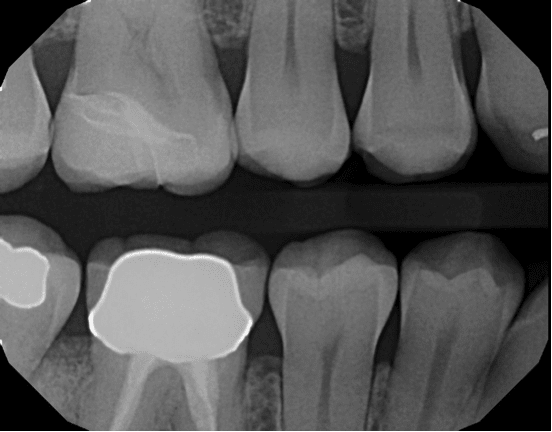

Taking a systematic approach to bur selection will streamline the chairside experience for the practitioner and the patient. In this case, I am prepping tooth No. 3 for a partial coverage restoration. It is a large filling with decay underneath. Whether it is partial (Figure 1) or full (Figure 2) coverage, preparation design should begin with the removal of the existing filling and any decay (Figure 3). This step is usually accomplished with the use of a Solo diamond double inverted cone. Once this step is complete, the clinician should either break contact with a flame or begin occlusal reduction with the football diamond. The preparation may require a build-up material to idealize the shape after the general form has been completed.

The preparation margins are then finished per the dental designer’s preference, which involves using burs and diamonds. The primary goal in bur selection is to choose a dependable, well-made, sterile, and predictable bur that will accomplish the best preparation. I prefer to use a shoulder preparation with a flat end taper, such as the Solo course grit 837012C or 837016C. The 12C and 16C signifies the diameter of the bur and is a useful tool in determining the amount of tooth reduction made on the axial walls. However, different clinical situations may require different burs, so dental designers should not limit themselves to one particular model or line.

It should be noted that Premier’s KR Modified Shoulder prep burs allow for a 90° margin with a rounded internal angle. This combination of burs allows me to prepare crowns, inlays, or onlays, and serves as my first choice for a restorative bur block. After tooth preparation is complete, the dentist must address whether retraction is needed. Clinicians can either place a retraction cord or use a paste retraction system like Traxodent® Hemodent™. Typically, I use both retraction cord and Traxodent, which better isolates the preparation for scanning and designing a CAD/CAM milled restoration. It also isolates the tooth for same day seating of the restoration, keeps the area clean before the procedure, and assists in a fast, easy cleanup of bonding materials.

I create same-day restorations using the Planmeca PlanMillTM 40 to produce a precise, smooth and well fitting restoration (Figure 4). Once the restoration is milled and tried in the patient’s mouth, the Two Striper finishing kit allows for the clinician to make any desired finishing touches (Figure 5 and Figure 6). For in-mouth finishing, I prefer to use Solo diamond finishing burs. If minor adjustments are required, the Premier Diamond Twist extraoral polishing system can also be utilized prior to cementation.

In this case, patient radiographs (Figure 7 and Figure 8) demonstrate a well-fitting CAD/CAM restoration that began with proper preparation design using the Solo diamond and efficient milling with the PlanMill 40. These tools can help clinicians provide ideal chairside tooth preparation, digital impressioning, and CAD/CAM milling, to ultimately deliver restorations of the highest quality.